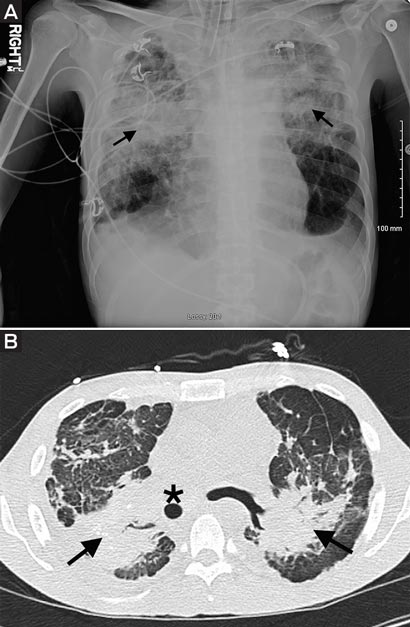

Chest auscultation identified bronchial breath sounds with crackles in the upper zones. Chest x-ray showed bilateral upper lung opacification representing extensive pulmonary consolidation and fibrosis (Figure, A), consistent with progressive massive fibrosis, confirmed by computed tomography (Figure, B).

A: Chest x-ray image of patient. Arrows indicate bilateral upper lung opacification. B: Computed tomography chest image. Mass-like fibrosis (arrows) and displaced trachea (star) are indicated.